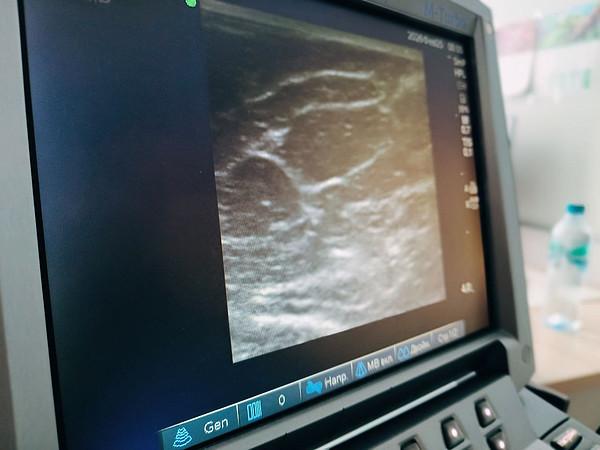

06.